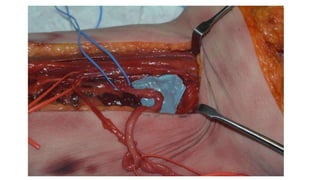

The document describes the surgical technique for harvesting a vascularised ulnar nerve graft. The dissection begins by incising over the flexor carpi ulnaris tendon proximal to the wrist. The nerve is identified and followed distally into the Guyon canal between the pisiform bone and hook of the hamate. Proximally, the nerve is followed into the olecranon notch and divided above the superficial ulnar collateral artery, ensuring a vascularized graft. The harvested ulnar nerve with vascular supply is then ready to be coapted to the target nerve.